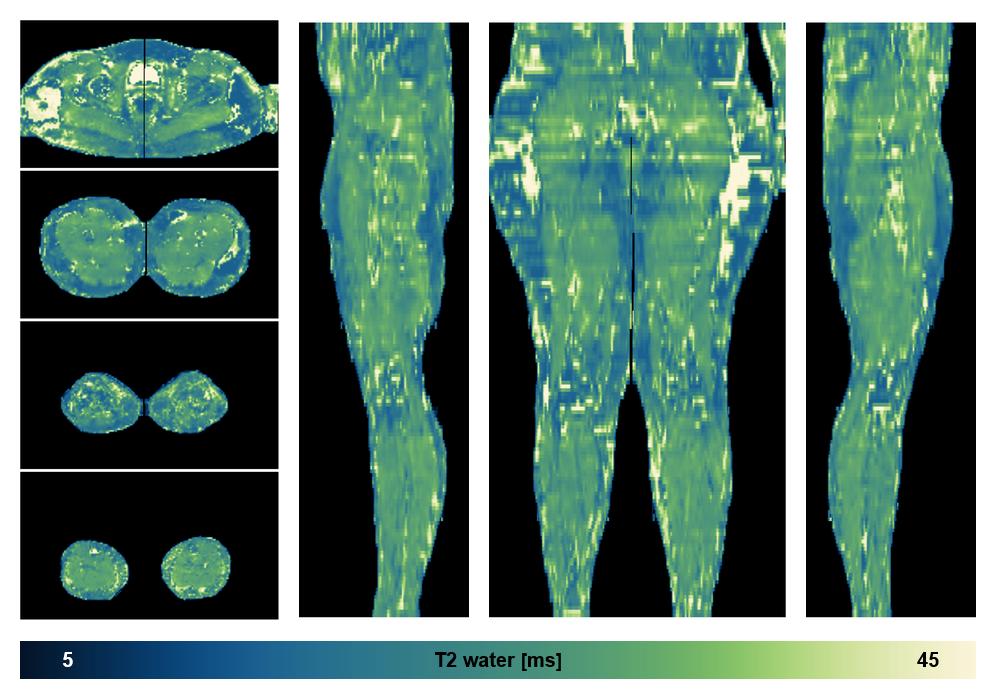

Water only T2 mapping

Multi echo spin echo T2 relaxation time mapping with EPG reconstruction, for information look here».

• Water only T2 relaxation time

The water only T2 relaxation time of the lower extremity obtained from multi echo spin echo t2 mapping with EPG based reconstruction.